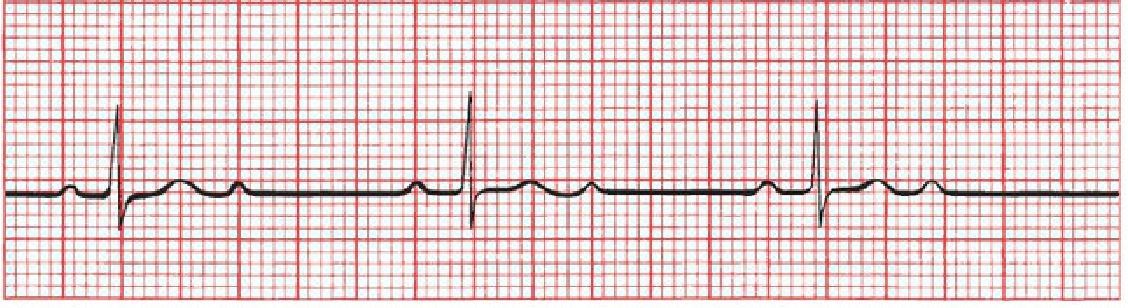

Is this NSR? If not, what is it?

Mobitz type I second-degree AV block (Wenckebach block). The PR intervals become progressively longer until one QRS complex is dropped.